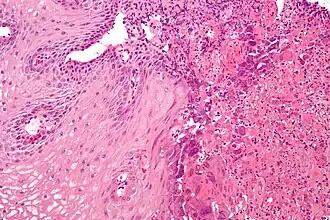

El término general esofagitis designa cualquier inflamación, irritación o hinchazón del esófago.[1] La esofagitis puede ser asintomática o puede causar dolor ardiente epigástrico o subesternal, especialmente al acostarse o hacer un esfuerzo, y puede dificultar la deglución (disfagia). La causa más común de esofagitis es el flujo inverso de ácido desde el estómago hacia la parte inferior del esófago: enfermedad por reflujo gastroesofágico (enfermedad por reflujo gastroesofágico o ERGE).[2]